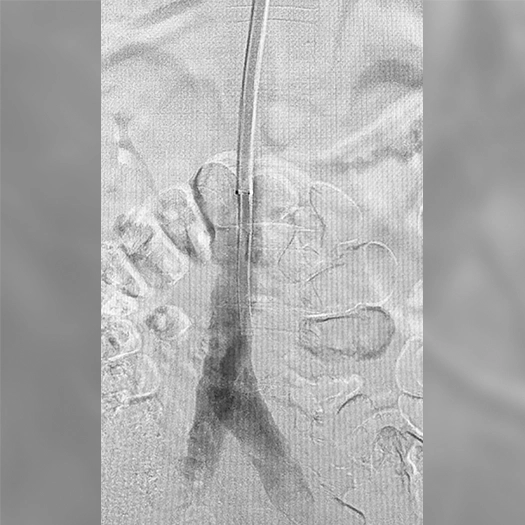

Venous Cases

Images used with permission and provided for illustrative purposes only. Procedural techniques and decisions based on physician’s medical judgment. Individual results may vary. Consents on file at Penumbra, Inc.